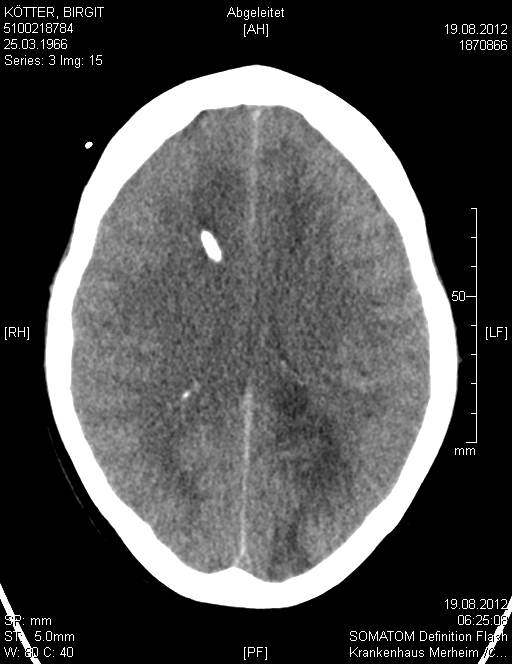

Nach dem multiplen Infarkt vom 19.08.2012 sind diese Strukturen nicht mehr erkennbar:

image12